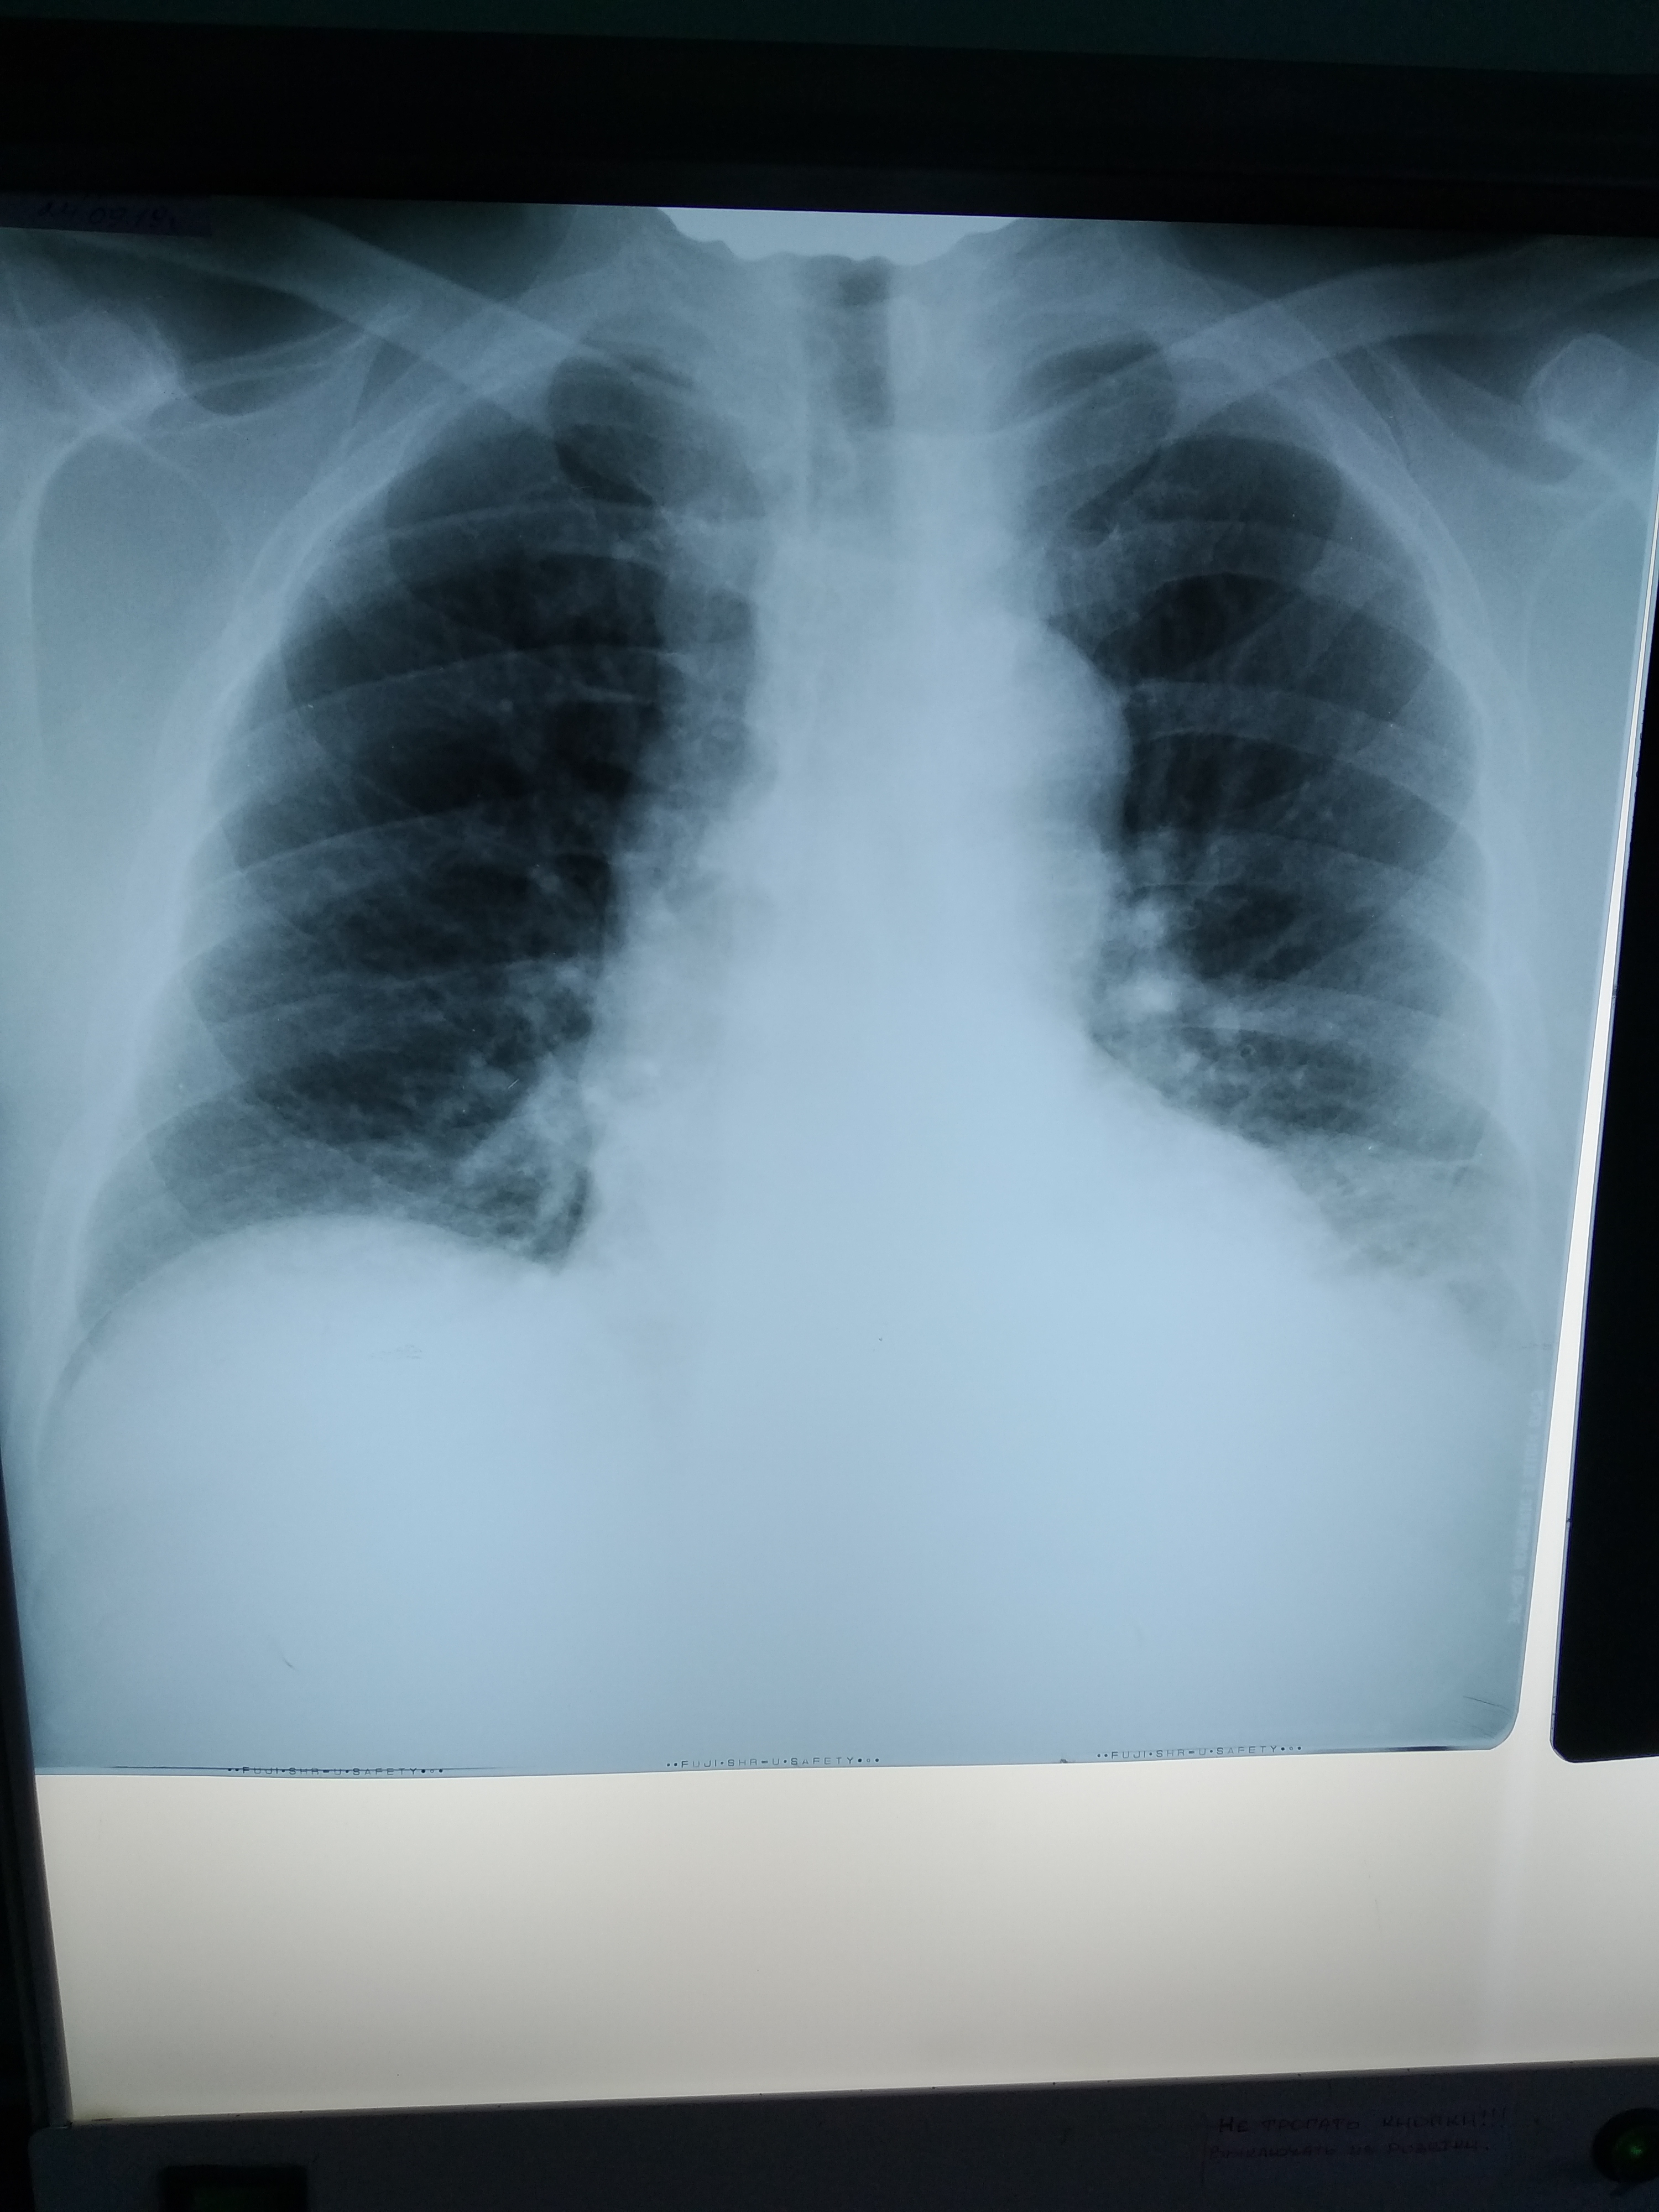

Пациент пришел на УЗИ ОБП с жалобами на сильную головную боль и головокружение. Температура тела нормальная, в крови 16 тыс. лейкоцитов.

Ателектаз левого легкого, исключить Са. Абсцесс?

У меня сложилось впечатление, что образование существует отдельно от лёгкого. Смущает его правильная овоидная форма, ровный контур, неоднородная структура и отсутствие ткани легкого (воздушного/безвоздушного) вокруг него. При ЦДК кровоток не определялся. КТ рекомендовала.

На представленных сканах не вижу нормальной ткани легкого. Плевральная жидкость довольно однородна для плеврита с цитозом 16К. Если эта штука не связана с легким, то мб свящана с плеврой - мезотелиома?

Похоже на опухоль с распадом и нагноением, ателектаз, гидроторакс/плеврит.

Рентгенограмму покажете?